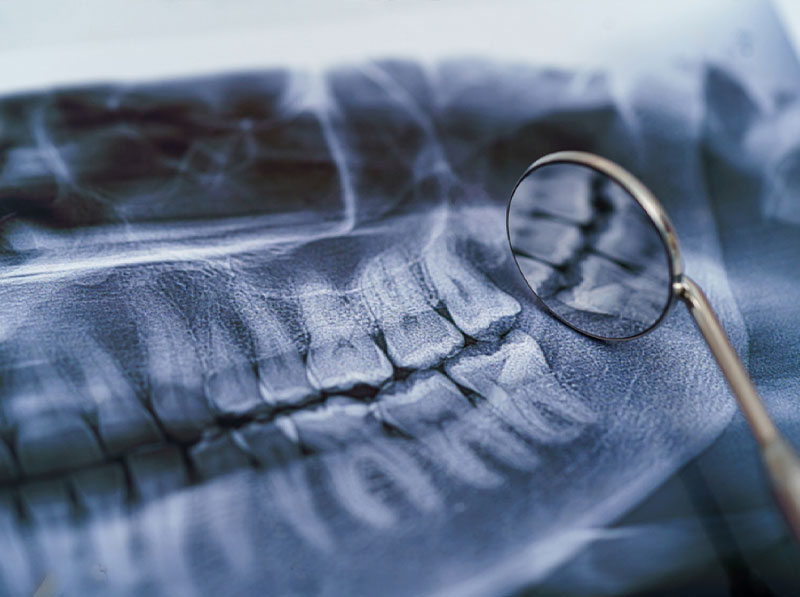

During your consultation with Dr. Steven Haywood, an extensive evaluation of your oral health will be performed, and 3D C.B.C.T. scans of your mouth and face will likely be taken. He will also educate you about the anesthesia or sedation options to be considered for your treatment to maximize comfort. He performs several different bone grafting procedures to meet his patients’ needs.

SHREWSBURY, PA ORAL SURGERYA dental bone graft is necessary when bone loss has occurred in the jaw, this procedure is commonly performed prior to dental implant placement or when bone loss is negatively affecting neighboring teeth

A dental bone graft is necessary when bone loss has occurred in the jaw, this procedure is commonly performed prior to dental implant placement or when bone loss is negatively affecting neighboring teeth